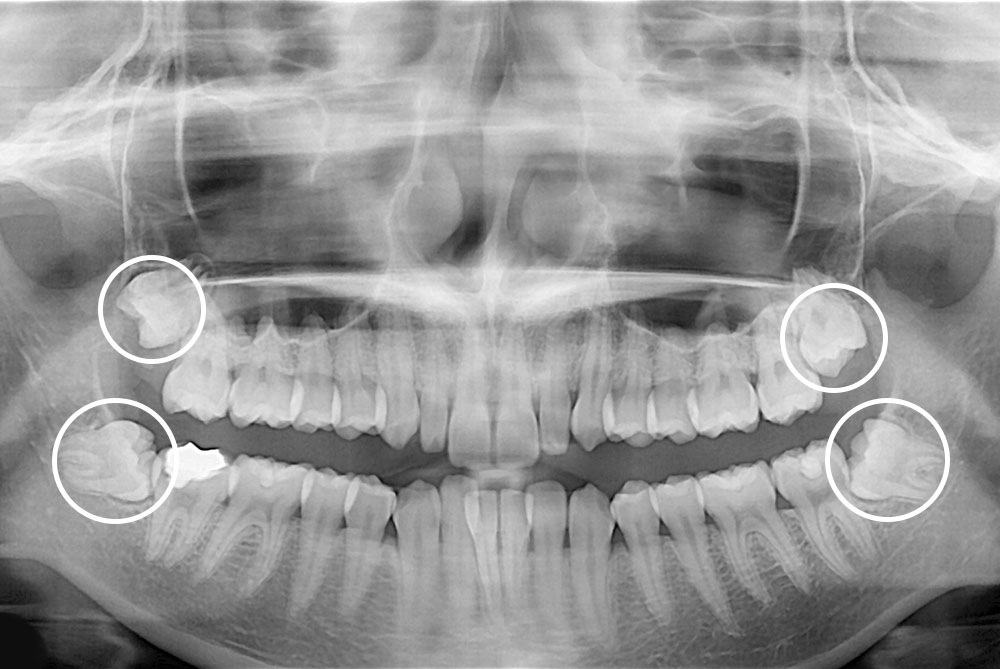

[사랑니] 매복 사랑니 발치

치료전 : 2019-01-30